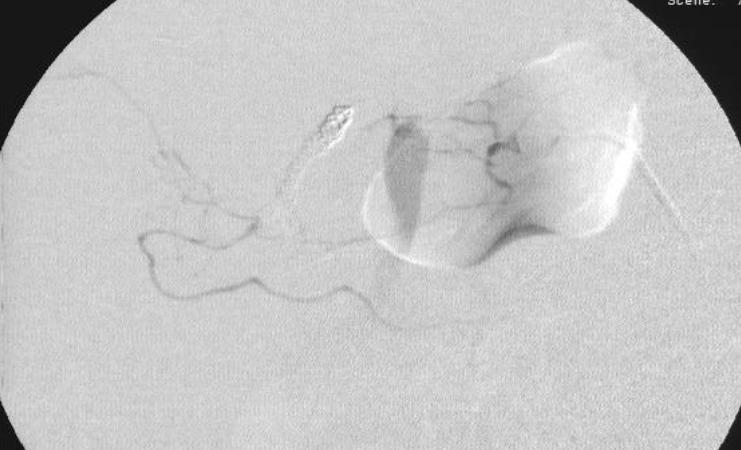

腹腔动脉造影也未发现出血 |

第二天病人持续出血,发现胰横动脉分支供血的部位出血(在PTCD管的左侧) |

选择性胰背动脉造影未见危险分支 |

微导管进入胰背动脉造影 |

注射n-BCA |

术后造影 |